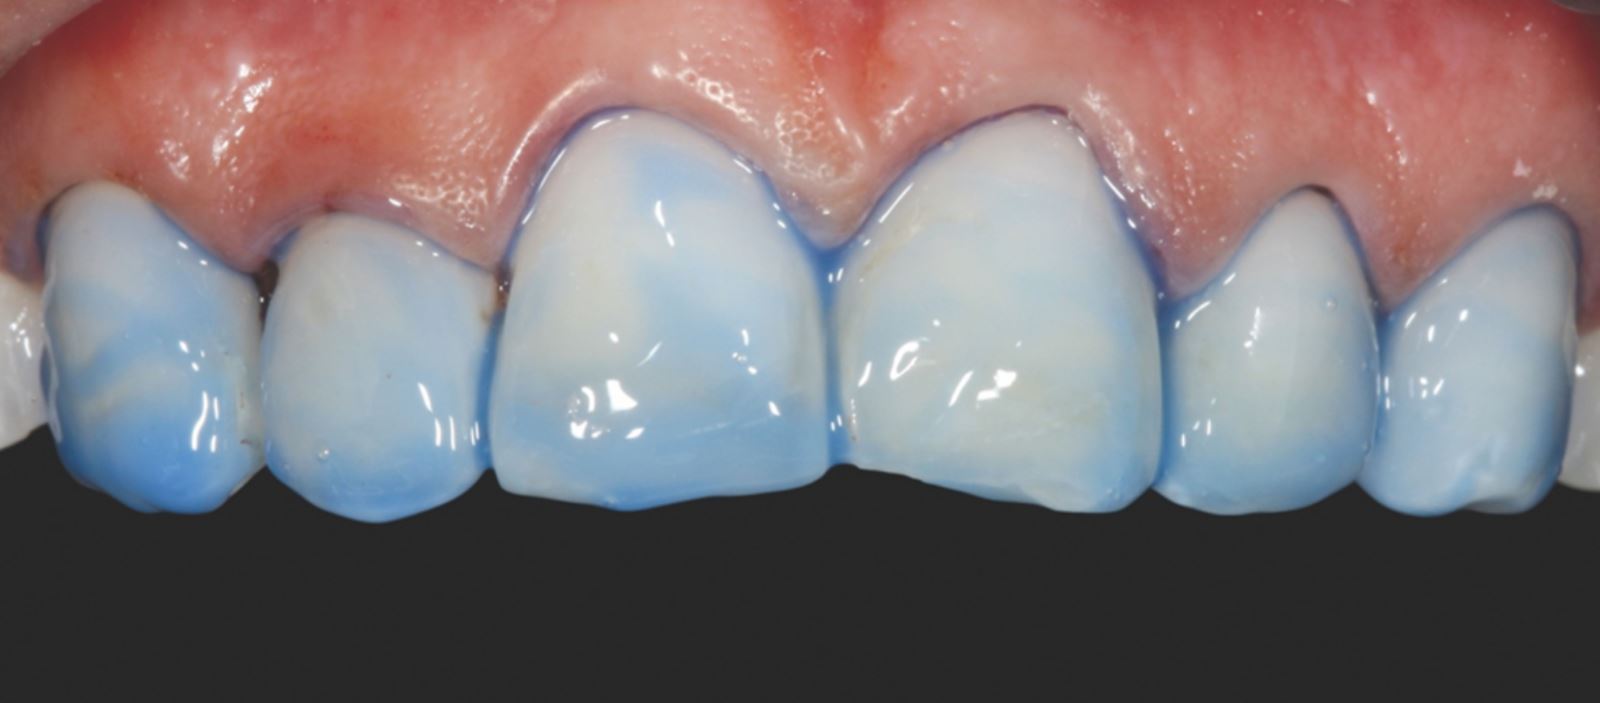

Leptanie nepreparovanej skloviny:

Nepreparovaná sklovina bola leptaná 35% kyselinou fosforečnou Ultra-Etch po dobu 30 sekúnd.

Aplikácia a stenčenie adhezíva:

Adhezívum Peak Universal Bond bolo aplikované a stenčené vzduchom so súčasným odsávaním.